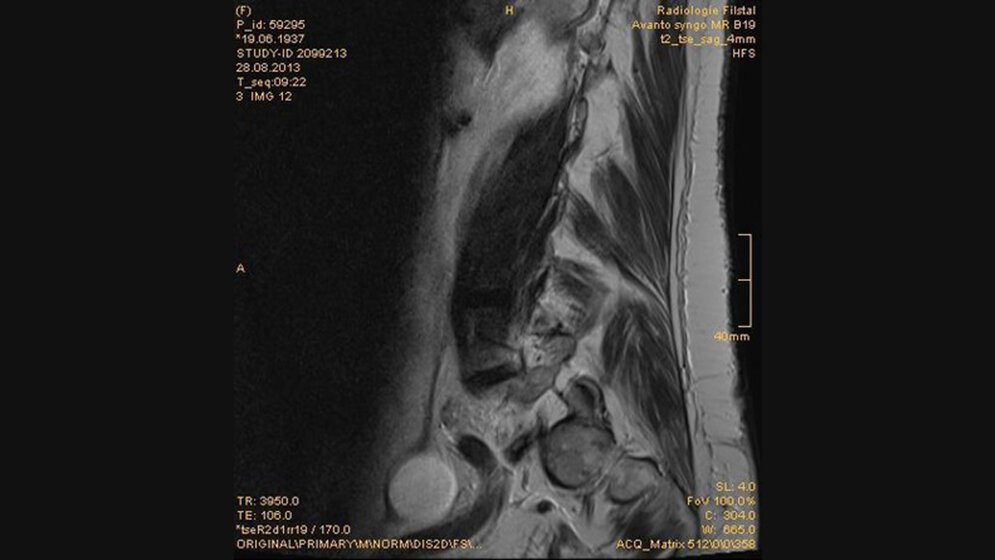

Schnittbilddiagnostik der Wirbelsäule (7.16)

Ovarialzysten können als liquide Formationen im weiblichen Becken mit unterschiedlicher Größe bei kernspintomographischen Untersuchungen als Zufallsbefund erfasst werden.

Der transvaginale Ultraschall ist die Methode der Wahl in der Darstellung von Adnextumoren. CT und MRT sind ergänzende Untersuchungsmethoden. Ovarialzysten können akute oder chronische Beckenschmerzen verursachen.